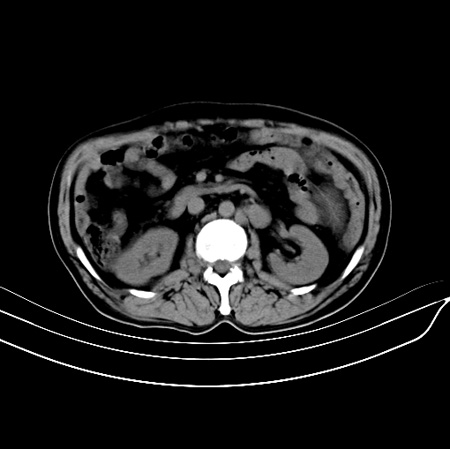

以下是引用江尾海头在2007-9-7 19:01:00的发言:[br]肝叶比例失调,肝边缘高低不平,尾状叶增大,肝裂增宽。肝右叶见较大密度减低影,边缘欠清。脾脏明显增大,胃底及奇静脉半奇静脉曲张。胆囊未见明显显示。 考虑:1、肝癌。2、肝硬化伴脾大静脉曲张。

以下是引用zhangxu5888在2007-9-7 22:31:00的发言:[br]1、肝硬化,食管 胃底及奇静脉半奇静脉曲张;2、脾脏肿大; 3、肝右叶的病灶呈锲性改变,内可见条片状钙化,边界清晰,密度明显低于周围正常肝组织,我觉得肝癌可能性不是很大, 同意楼上观点,有可能是栓塞,建议增强.